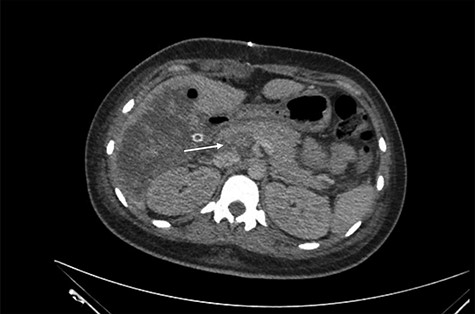

She was referred to our center on postoperative Day 4 due to progressive jaundice and encephalopathy. A triphasic contrast-enhanced abdominal computed tomography (CT) was done revealing a right liver lobe infarct, absence of the right and left hepatic arteries (Fig. 1), presence of an accessory left hepatic artery from the left gastric artery (Fig. 2) and right portal vein thrombosis with extension to the main portal vein (Fig. 3).

Main portal vein thrombosis (white arrow) on portal phase of the triphasic contrast-enhanced abdominal CT.